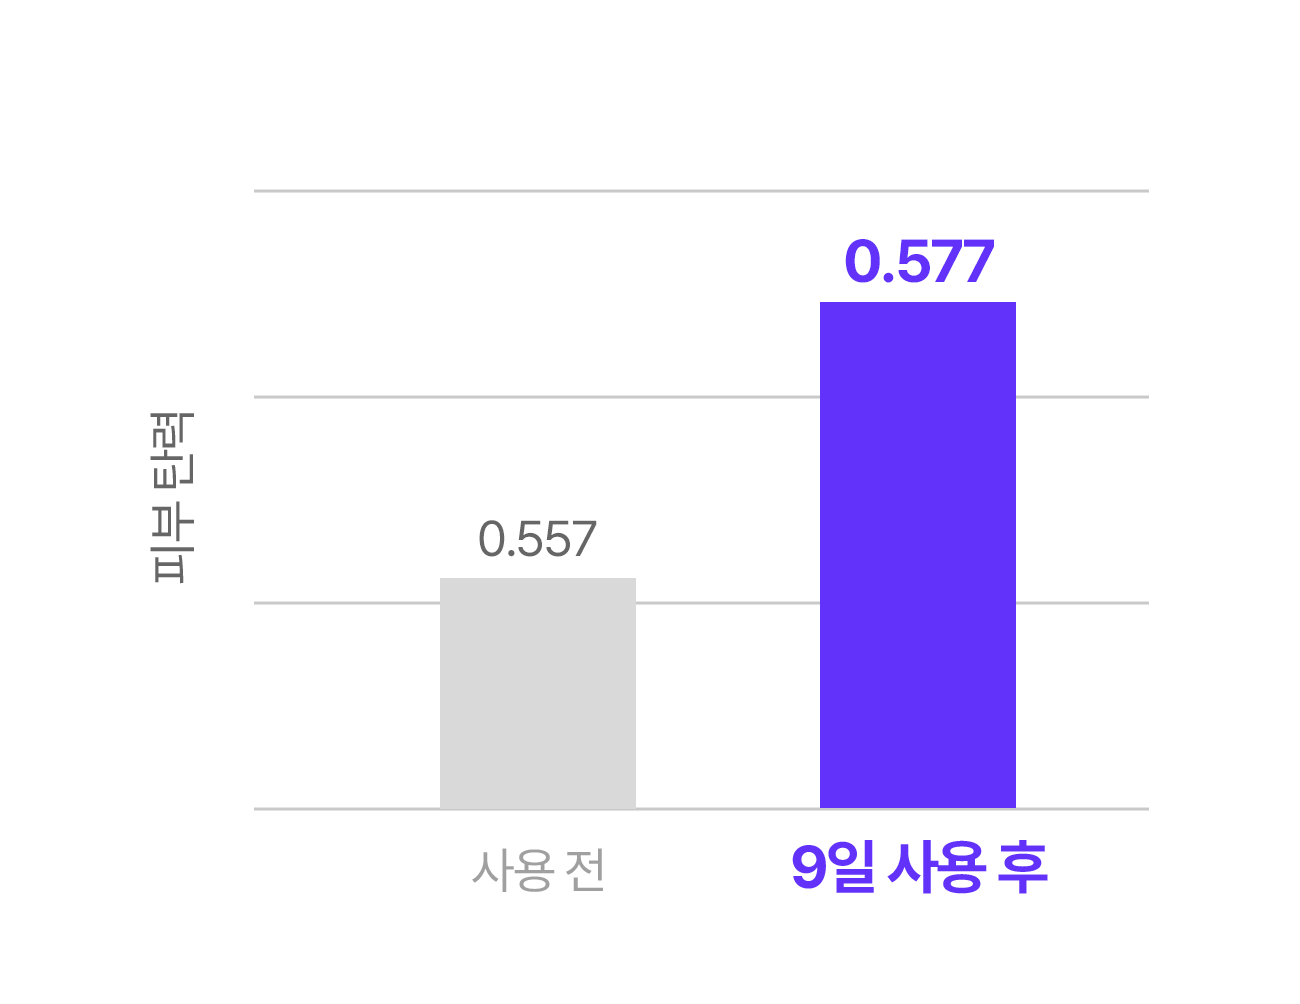

Q1. 정말 9일만에 효과를 느낄 수 있나요?

A. 실제 임상 실험과 소비자 테스트 결과, 피부톤 개선과 잡티 완화에 있어 9일 안에 변화를 체감한 사용자가 많았습니다. 물론 개인 피부 상태에 따라 차이는 있을 수 있으나, 빠른 효과를 목표로 설계된 제품입니다.